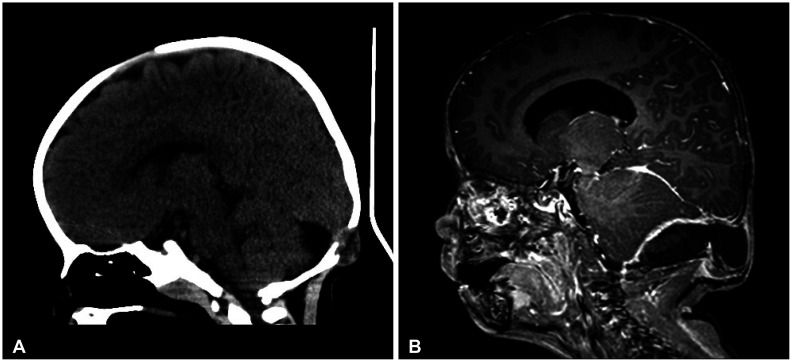

Eosinophilic granuloma (EG), a subtype of Langerhans cell histiocytosis (LCH), the monostotic form, is a rare condition characterized by a solitary bone lesion. It is even more unusual for this condition to be accompanied by an epidural hematoma (EDH). This case is unique in that it is the first to involve delayed EDH following a seizure. We describe a remarkable example of EG accompanied by an EDH and consider the rarity of this comorbidity. A 32-month-old boy developed a rapidly growing skull mass following a minor head injury. During surgical preparation for a biopsy, the patient experienced a single convulsion. Imaging following the seizure revealed an EDH in the vicinity of the mass. The mass was excised and confirmed to be an EG, but with positive margins. The patient underwent chemotherapy after systemic skeletal evaluation, in accordance with the LCH III protocol established by the Histiocytosis Society. EG is a rare neoplasm that typically presents as a painless growth on the skull that gradually enlarges over time. The correlation between EG and EDH is exceedingly uncommon, with only a few documented cases. This case study underscores the significance of considering EG in the differential diagnosis of an expanding cranium mass, even when associated with EDH. Prompt diagnosis and treatment can prevent serious complications and improve patient outcomes.